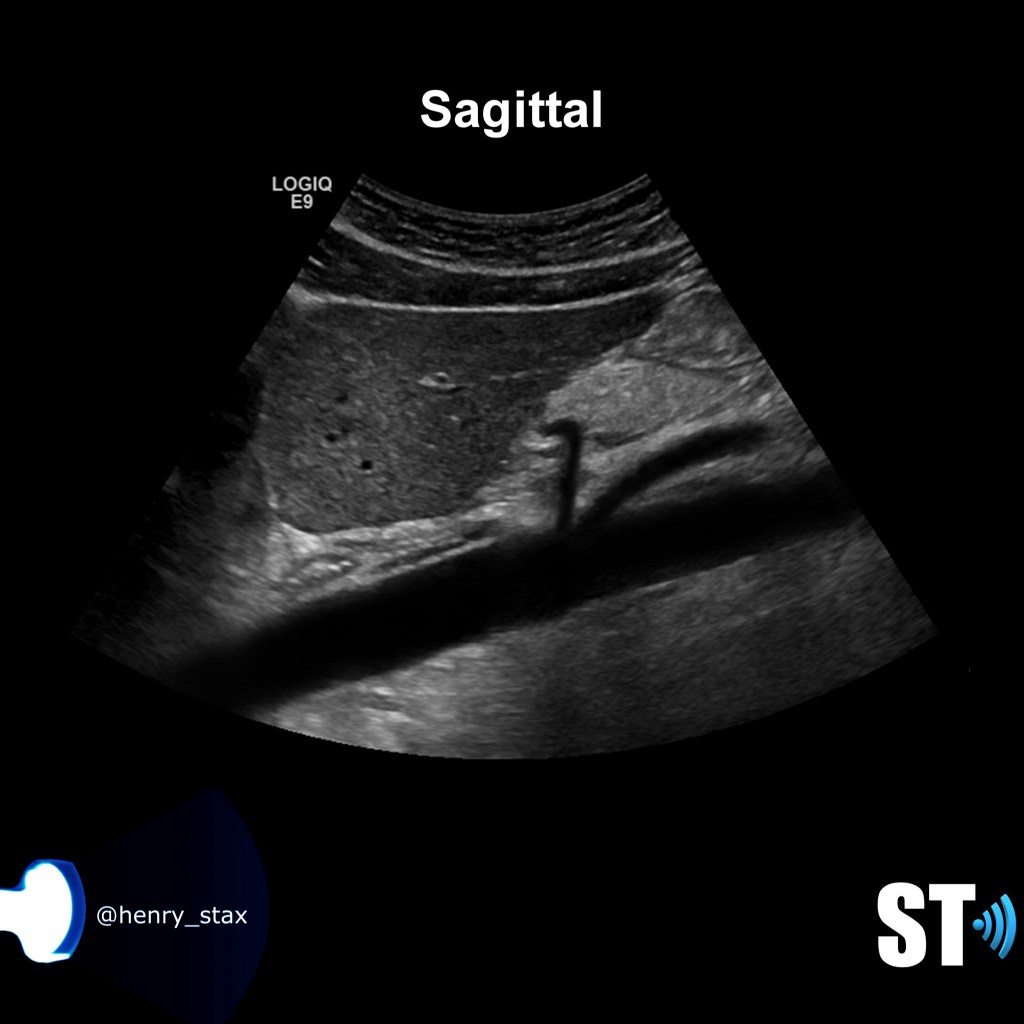

Ultrasound

Sonography is an important tool in evaluating kidneys for size, shape, location and echogenicity. Compared to other modalities it is the most cost effective. It is very adept at discovering lesions and various causes of hematuria i.e. nephrolithiasis, tumors etc.. With ultrasound we evaluate the kidneys and the urinary bladder and other retroperitoneal structures. With color doppler you can interrogate the aorta, ivc, renal arteries and veins which is of paramount importance in discovering renal vein compression, renal artery stenosis and renal vein thrombosis to name a few.

Sonographically there will be an acute aortomesenteric angle <36°

Measure the compression ratio = P-C/C (P = pre-compressed vein C= compressed vein, CR >2.25 is indicative of NCS). Image the vessels in sagittal and transverse